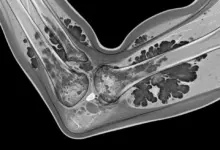

- Ressonância magnética: método de escolha para mapear o acometimento sinovial; costuma exibir áreas com depósito de pigmento e realce após contraste.